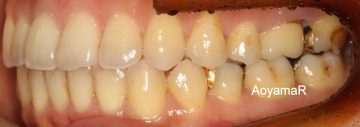

開咬(前歯が開いている、オープンバイト)の矯正症例

CASE 12

(37歳 女性 )

マウスピース型カスタムメイド矯正装置(インビザライン)単独による治療

治療前

治療後